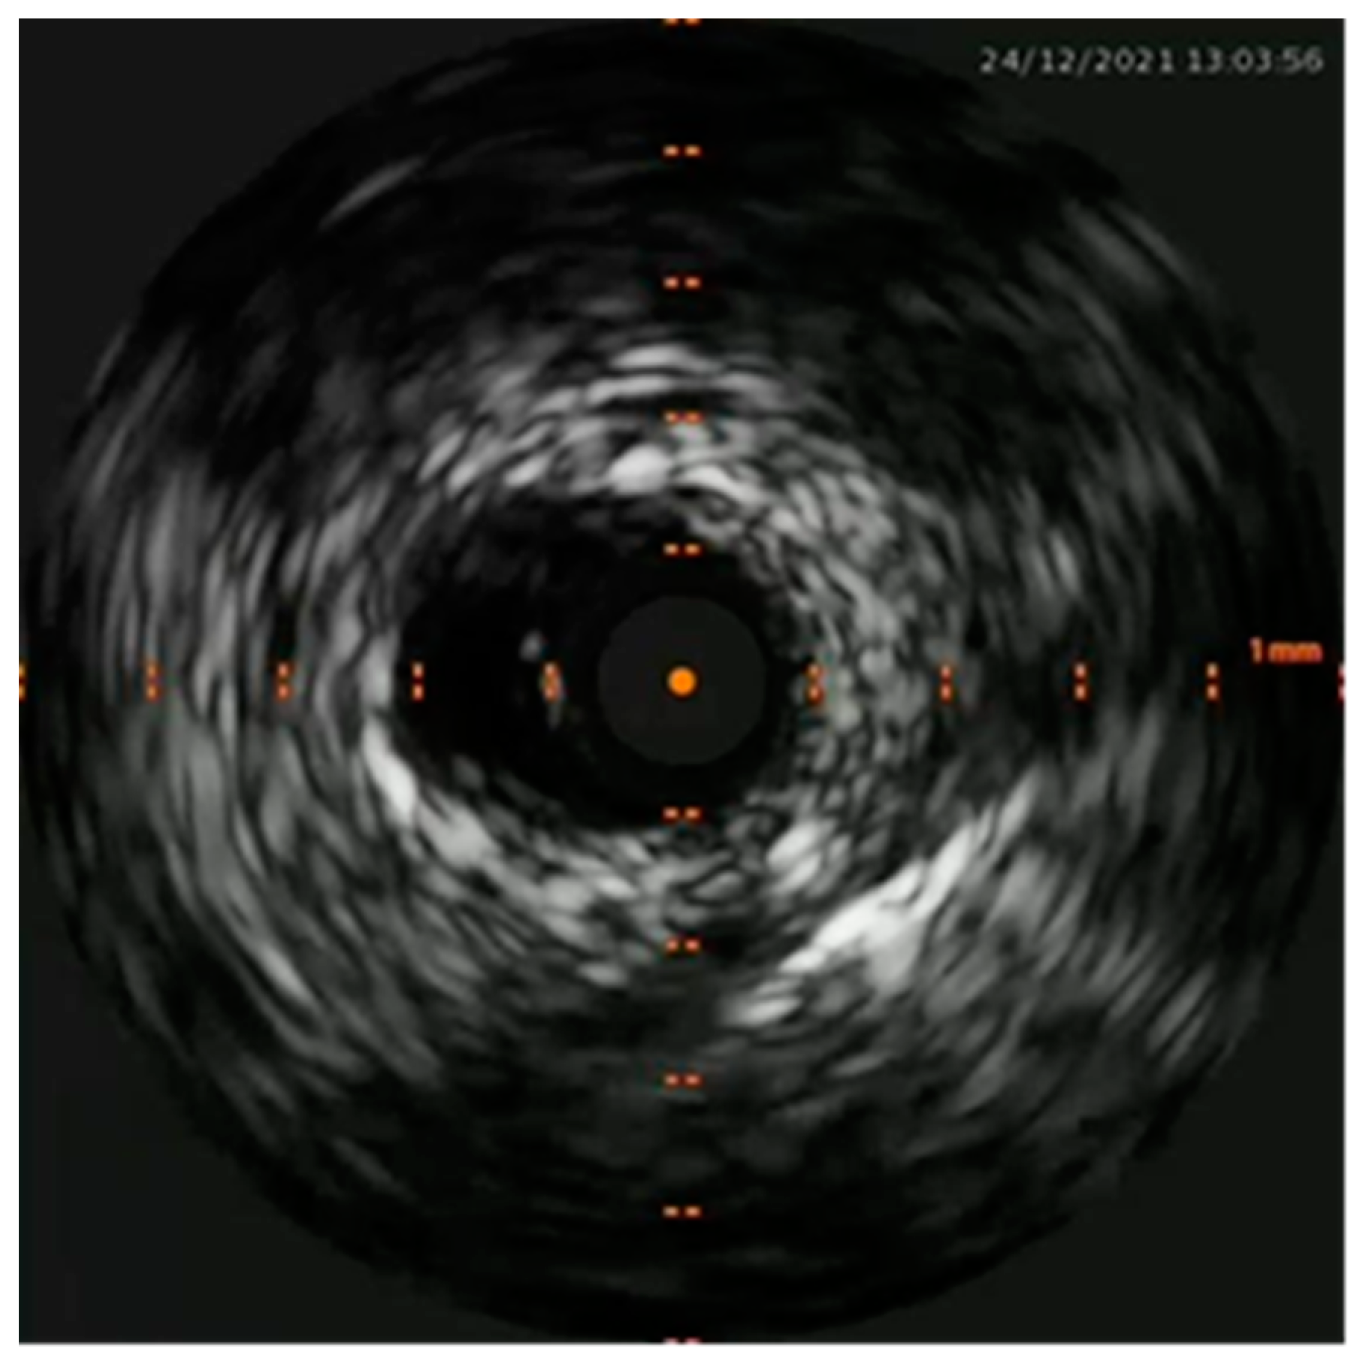

M.G. is a 38 years old woman with two previous pregnancies (G2P2), who was 36 weeks of gestation in her third uneventful pregnancy. All the ultrasound scans (US) performed highlighted a regular fetal growth and normal placental functional markers (umbilical Doppler Pulsatility index), Figure 1 and Figure 2. Her only known risk factor is smoking, which she had temporarily quitted.

Figure 2. Sonogram depicting a normal umbilical doppler Pulsatility Index during the third trimester ultrasound scan.